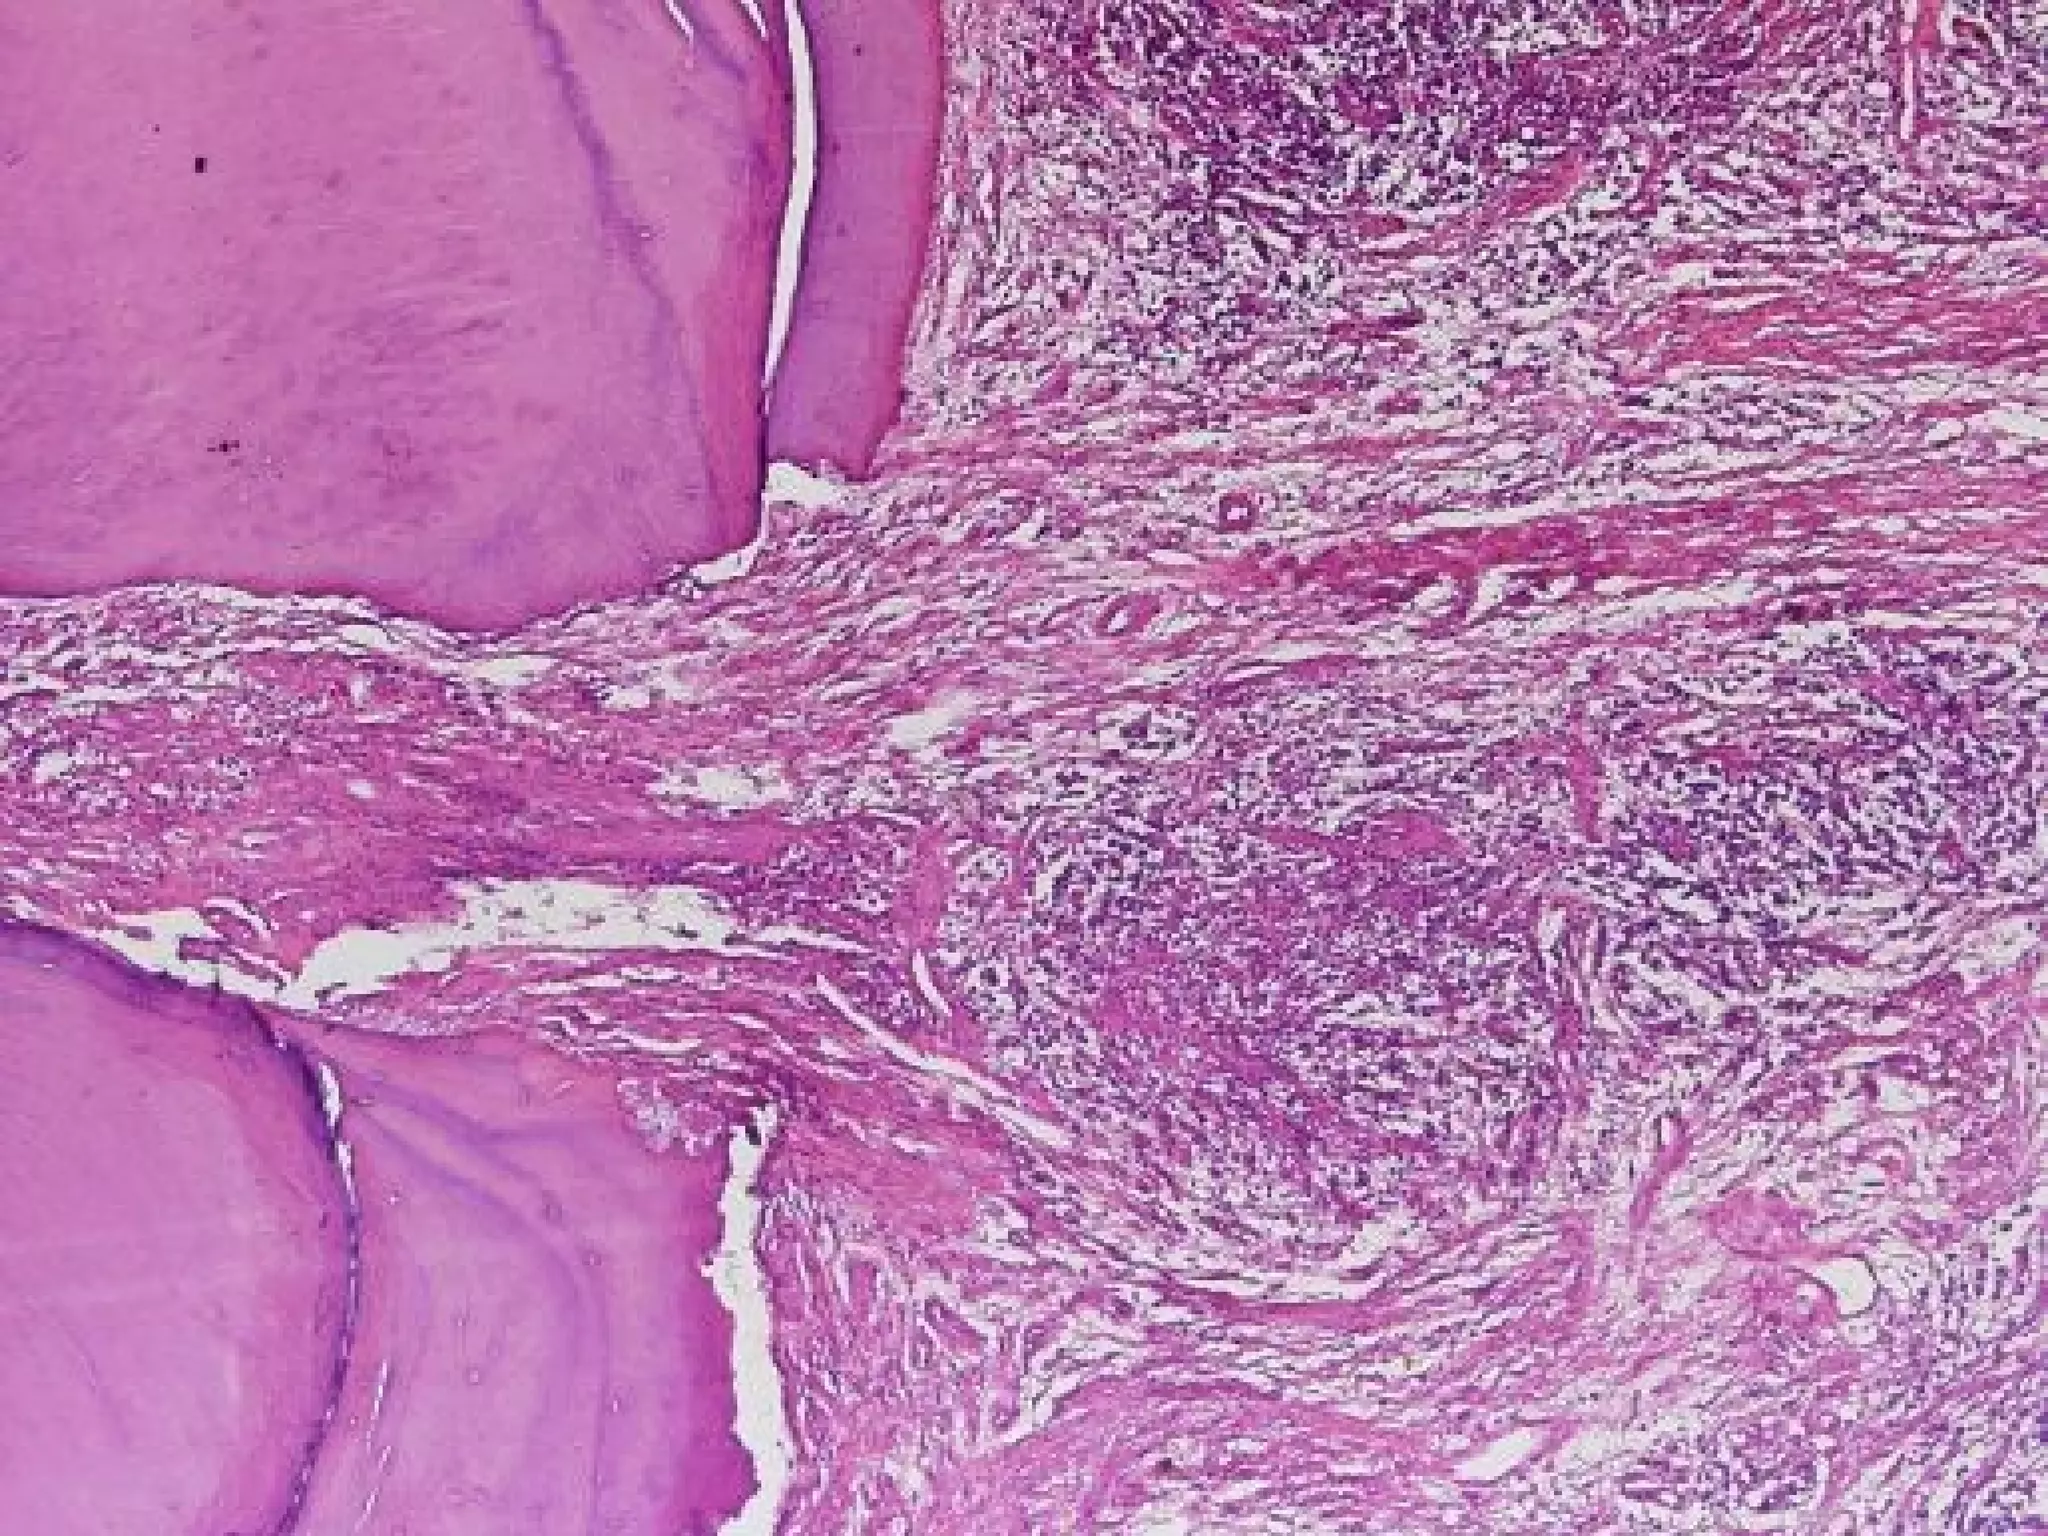

Chronic Hyperplastic Pulpitis

Pulp Polyp

 Histopathological

Features:

 The

polyp consists of granulation tissue.

It contains delicate connective tissue, fibers

and blood vessels.

Mononuclear inflammatory cell infiltration.

The polyp is covered with SS epithelium.